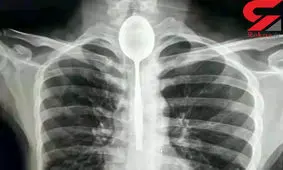

مردی در یک شرط بندی احمقانه قاشق 20 سانتی را بلعید و از آنجایی که مشکلی در خوردن و آشامیدن نداشت تا یکسال این قاشق داخل گلوی وی ماند.